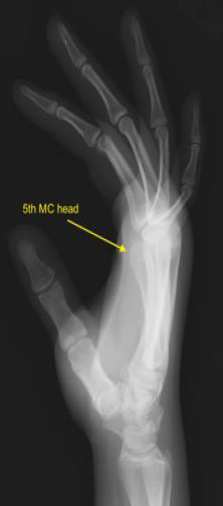

(This image, likely depicting K-wire or plate fixation for finger CMCs, fits well here.)

Finger CMCs (Second to Fifth CMCs) Injuries

These joints are typically approached dorsally. Protecting extensor tendons and dorsal sensory nerves is crucial.